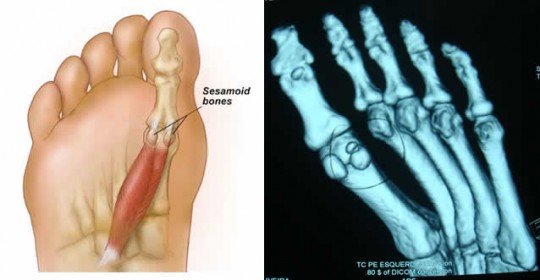

Les os sésamoïdes sont au nombre de deux, et sont situés dans l’articulation du gros orteil (aussi appelé l’hallux).

Ils ont un rôle primordial en phase terminale du pas, où tout le poids du corps repose dessus, ce qui leur fait subir de fortes contraintes.